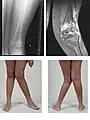

Set forfra danner lårknoglen (femur) og skinnebenet normalt en vinkel på 175° i forhold til hinanden. Folk der er kalveknæede har en mindre vinkel (genu valgum) og folk der er hjulbenede har en større vinkel (genu varum).

En kalveknæet mand.

Røntgenbillede af en to-årig med engelsk syge.- Real-time MRI af et knæ.